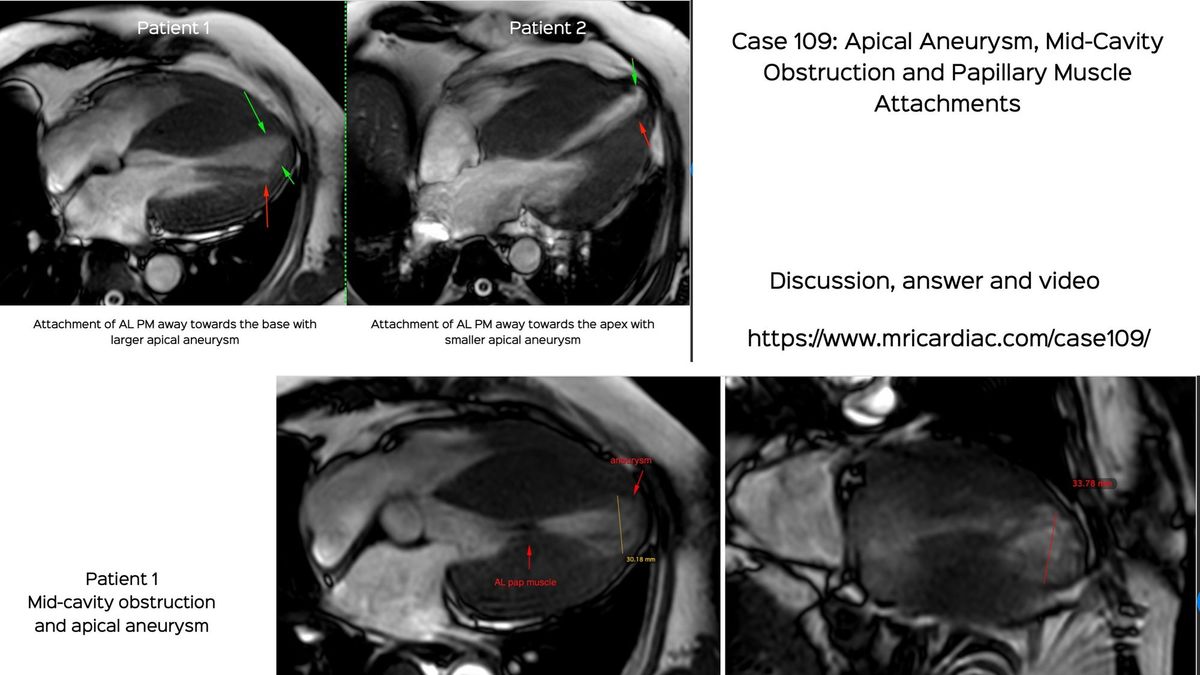

Case 109: Apical Aneurysm, Mid-Cavity Obstruction and Papillary Muscle Attachments

It is important to understand and diagnose apical aneurysms, infarcts, mid-cavity obstruction and associated changes

This case discusses two patients, both with apical aneurysms and mid-cavity obstruction and different papillary muscle attachments.

Based on a new article in JACC:Cardiovasc Imag by Mark Sherrid and colleagues and the accompany editorial by Milind Desai and colleague, I continue the discussion that I had started on apical HCM, in case 96.

The video discusses both these cases, the findings and the implications.